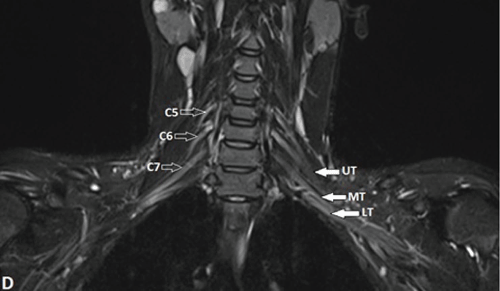

| Figure 1: Normal MR imaging planes and appearance of BP. A-F, Acquisition of the coronal plane with fat-suppressed T2-weighted anterior (D), mid (E), andposterior (F) coronal sections. First a coronal cervical spine scout is obtained (A), based on this a sagittal T2-weighted spin-echo sequence of the cervical spine isacquired (B). Now based on this sagittal image, coronal fat-suppressed T2-weighted and T1-weighted sequences are obtained in a plane parallel to the long axis ofthe lower cervical vertebrae (C) because the BP is oriented in an oblique coronal plane. On coronal fat-suppressed T2-weighted sequence, long axis of the nerveplexus is seen as elongated, uniform calibre, mildly hyperintense fascicular structure. On the anterior coronal image, normal C5, C6, C7 nerve roots (open arrows)are seen on the right side; on the left, the upper (UT), middle (MT) and lower trunks (LT) (solid arrows) are seen (D). At the level of middle scalene muscle (star), onthe mid-section, C8 ventral ramus (open arrows) is seen bilaterally (E), while the T1 nerve root (open arrows) is visualized completely on the posterior section (F). | |